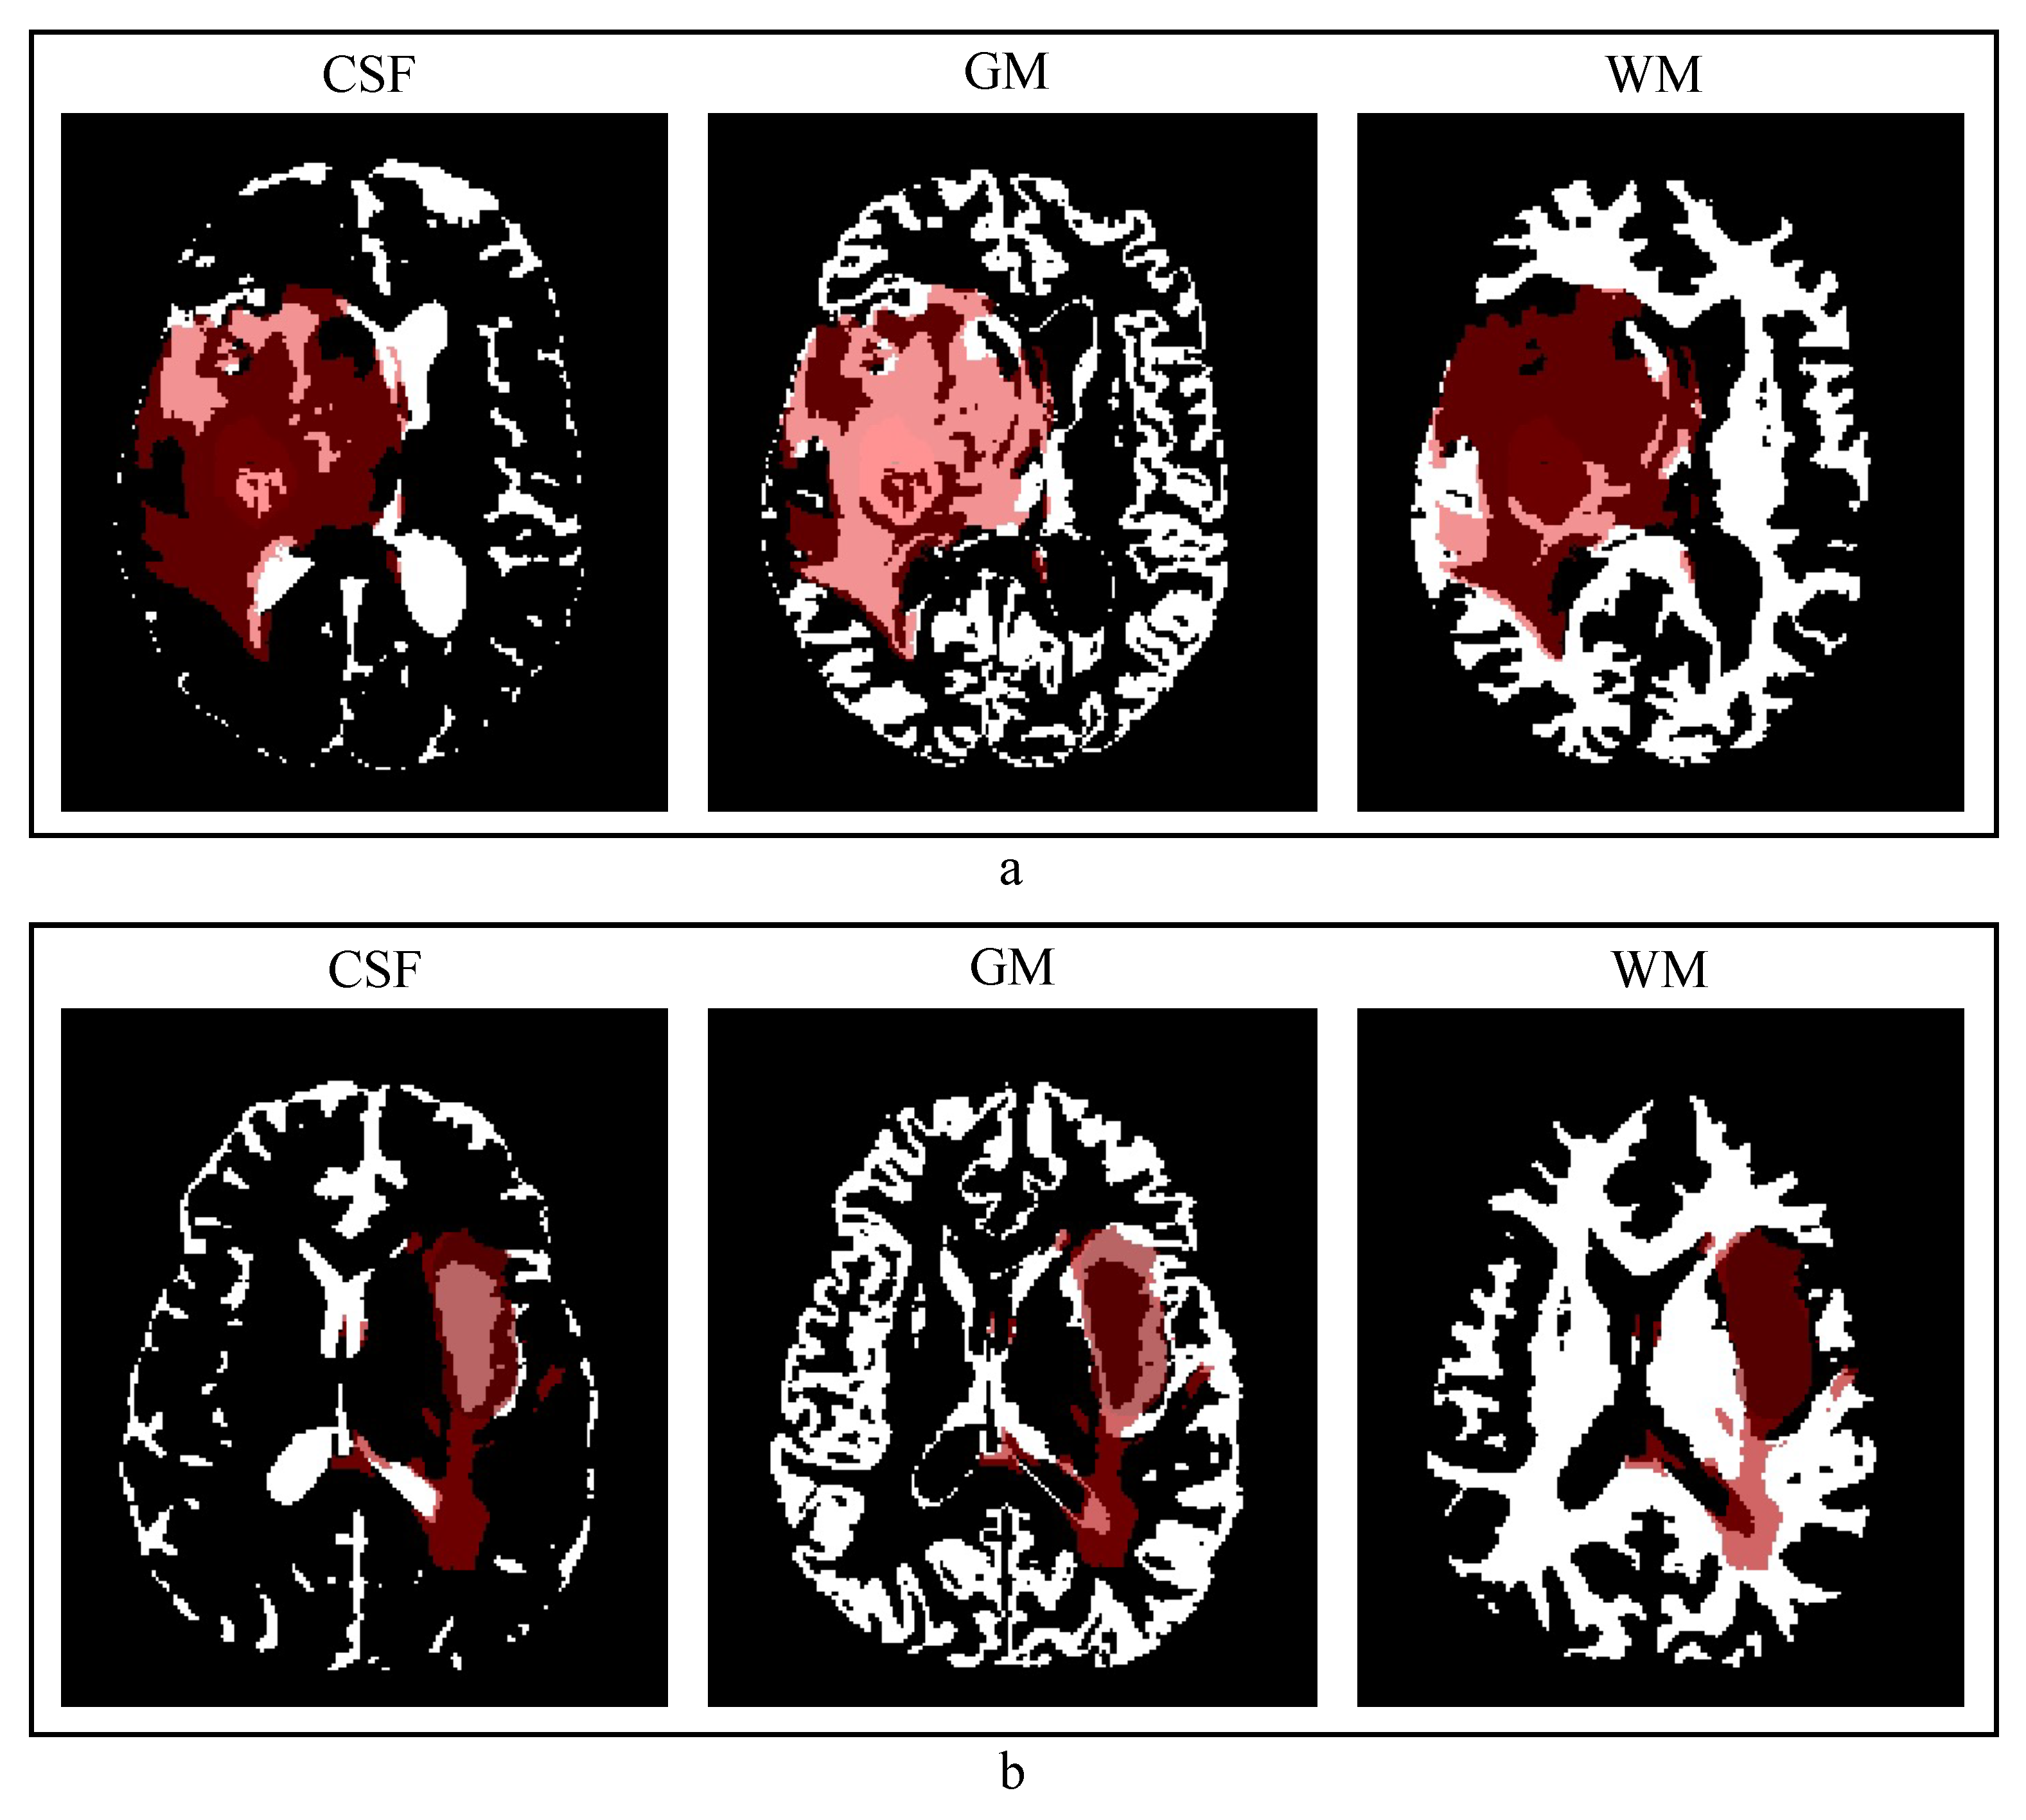

2.2. Anatomical Contextual Information